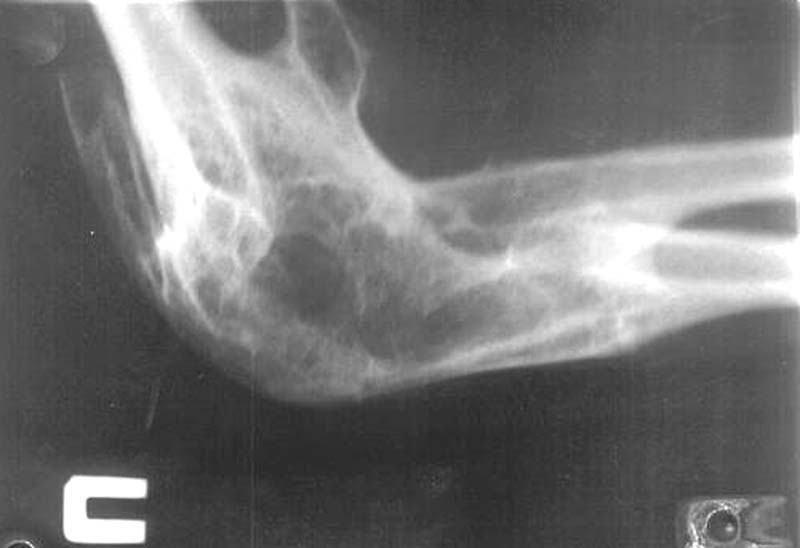

Из одного из городов нашей области к нам обратились родственники пациентки с вопросом о возможности оперативного вмешательства на локтевых суставах.К сожалени, мы ничего предложить не смогли. Ваше мнение? Каким может быть дальнейшее (оперативное, консервативное) лечение?

Женщина, 22 года, инвалид 1-й группы. В анамнезе парезы и плегии из-за разрыва аневризмы головного мозга и последующего ишемического спазма сосудов головного мозга при повторной операции. Дз: остаточные явления обширной двусторонней ишемии мозга вследствие оперативного вмешательства по поводу аневризмы ПСМА (2001 г.), нижний глубокий спастический парапарез, нейрогенные дисфункции тазовых органов, контрактуры локтевых, коленных и голеностопных суставов.КТ головного мозга: кистозно-атрофические изменения в обеих лобных долях (без динамики с 2002 г.), постинсультная киста в области колена внутренней капсулы базальных ядер справа, гипотрофические изменения в полушариях большого мозга.